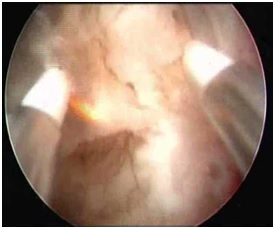

Внутриматочную перегородку по ее центру от вершины к основанию рассекали Г-образной петлей резектоскопа, последовательно, короткими движениями, монополярным током мощностью 60 – 80 Вт в чисто режущем режиме. Перегородку иссекали до формирования гладкой полости матки. Объем вводимой жидкости не превышал 6 литров; скорость подачи жидкости от 150 – 400 мл/ мин, среднее давление в полости матки – 60 – 80 мм.рт.ст. В послеоперационном периоде пациенткам в течение трех месяцев назначали гормональную контрацепцию. Метод гистероскопии расширяет диагностические возможности выявления внутриматочной патологии и выполнять оперативные манипуляции в полости матки. Окончательная диагностика внутриматочной перегородки возможна при одновременном выполнении гистеро- и лапароскопии.